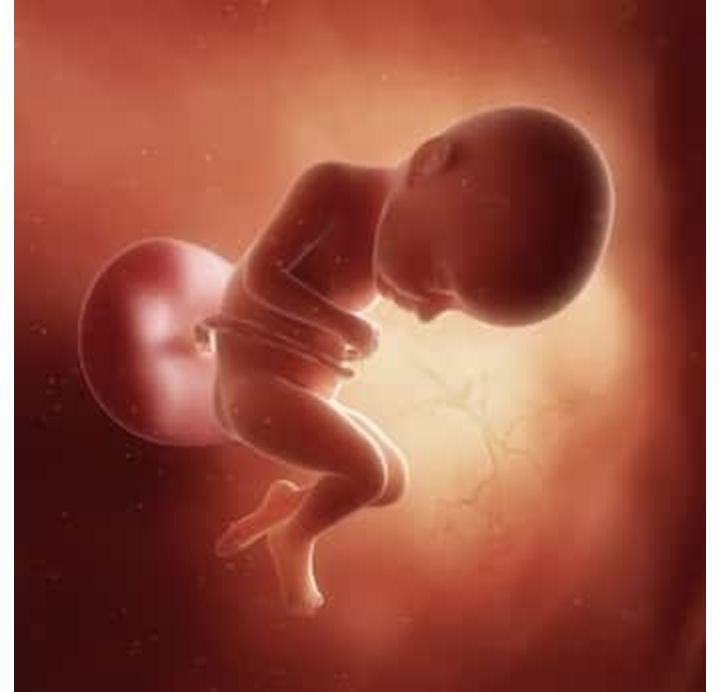

孕32周的胎宝宝有冬瓜那么大了,从头部到臀部长约43.6CM,约1868G▼:

孕32周的双胞胎胎儿发育图▼: